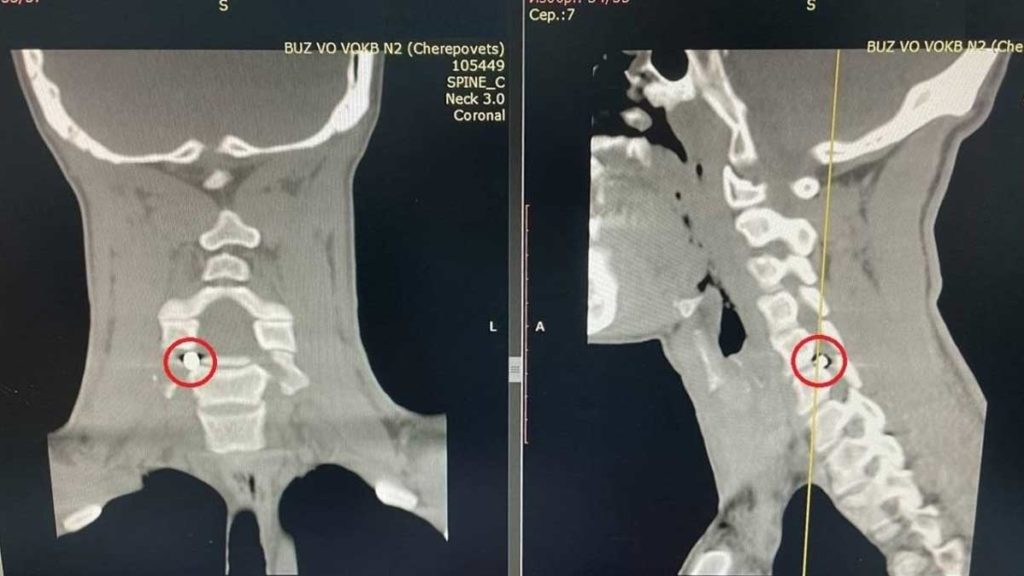

При проведении спиральной компьютерной томографии врачи выявили осколок размером 5×4 мм, расположенный в позвоночном канале. Фрагмент снаряда сдавливал корешок спинного мозга, что приводило к выраженной боли, иррадиирующей в руку, а также к онемению и снижению силы кисти.